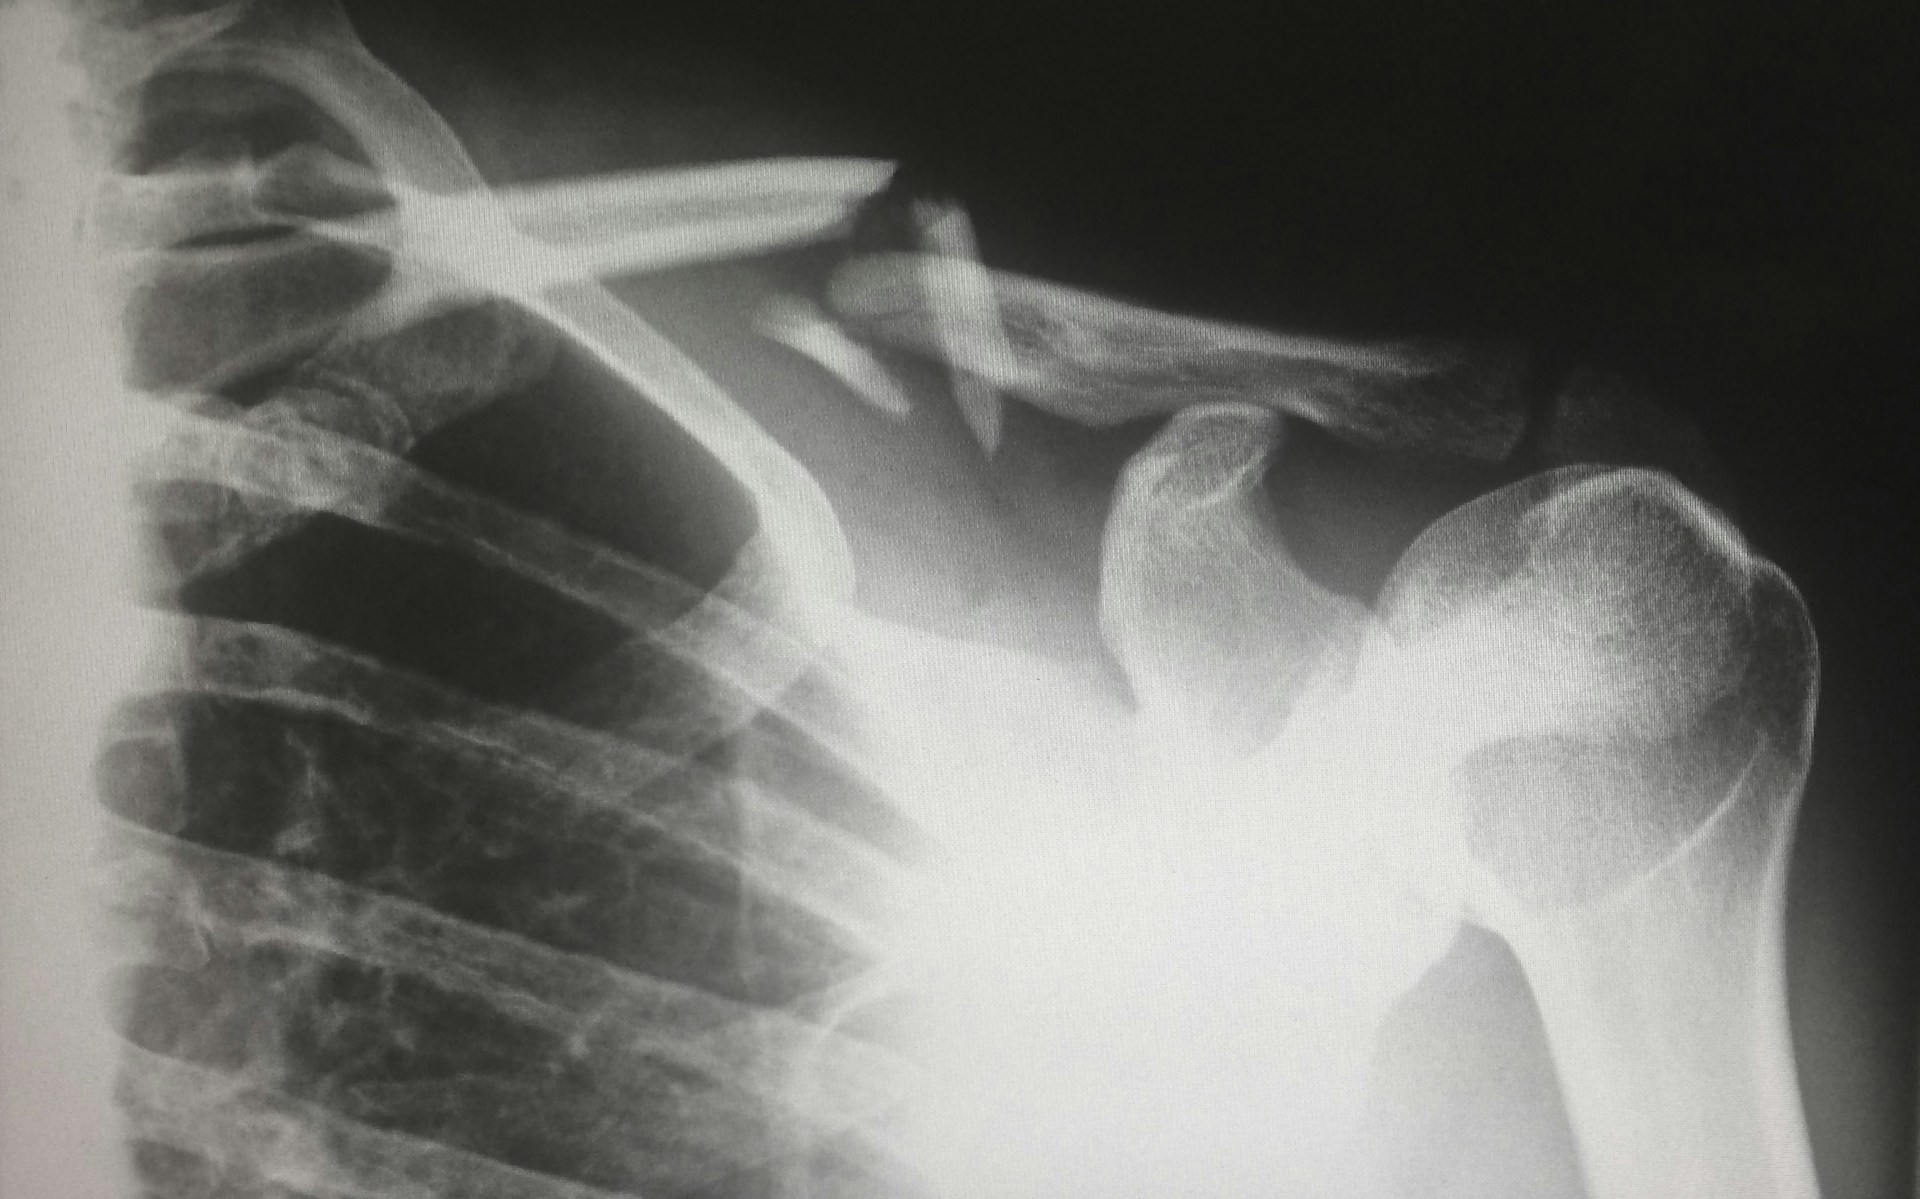

Indiferent de experiența pe care o aveți la ski, corpul are nevoie de încălzire corespunzătoare. Skiatul este ca orice activitate fizică pentru care corpul are nevoie de încălzire pentru a putea face față presiunii și a evita accidentările. În acest mod, puteți evita accidentări serioase în zona umerilor sau membrelor inferioare pentru care puteți avea nevoie de investigații amănunțite, cum ar fi artroscopie la umar, urmată de tratament îndelungat.